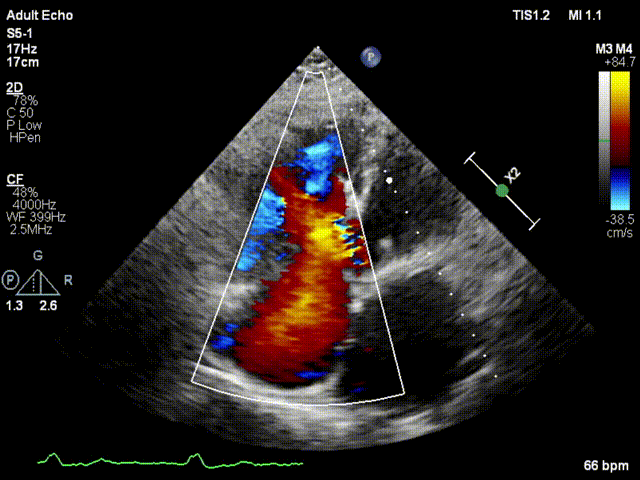

本次接受治療的患者是一名74歲的女性,14年前因風濕性心臟病行二尖瓣生物瓣植入術,合并房顫。近3年來反復因腹脹、納差、下肢水腫入院,藥物治療欠佳。心臟超聲顯示三尖瓣極重度反流(有效反流口面積:0.76cm²,反流容積:79ml),繼發性右房室增大及上、下腔靜脈增寬(右房上下徑*左右徑:52*41mm,右室左右徑:46mm,下腔靜脈:29mm),右室收縮功能正常,肺動脈收縮壓 43mmHg,左心室射血分數73% ?;颊呒韧_胸手術史,術前評估STS 評分為7.02分,CRS 9分,無法接受體外循環下三尖瓣外科手術。面對這一傳統治療無法解決的困境,葛均波院士及其團隊周達新教授、潘文志教授、張源博士、陳莎莎博士及心超室的潘翠珍教授、李偉教授經過討論決定,采用創新的Lux-Valve Plus系統為患者進行經血管三尖瓣置換。

手術在患者全麻狀態下進行,采用經右側頸靜脈作為入路,將裝載有人工瓣膜的輸送器緩慢推送至右心房;并在經食道超聲和DSA的引導下小心調整輸送器角度,將輸送器送入右心室;逐步釋放瓣膜錨定裝置和盤片,調整瓣膜位置后,錨定瓣膜完成植入。術后右房壓明顯下降,從術前的25/10(16) mmHg降至術后即刻的12/7(10) mmHg,術后超聲提示人工三尖瓣同軸性良好,固定牢固,無反流及瓣周漏,手術室即刻拔除氣管插管。